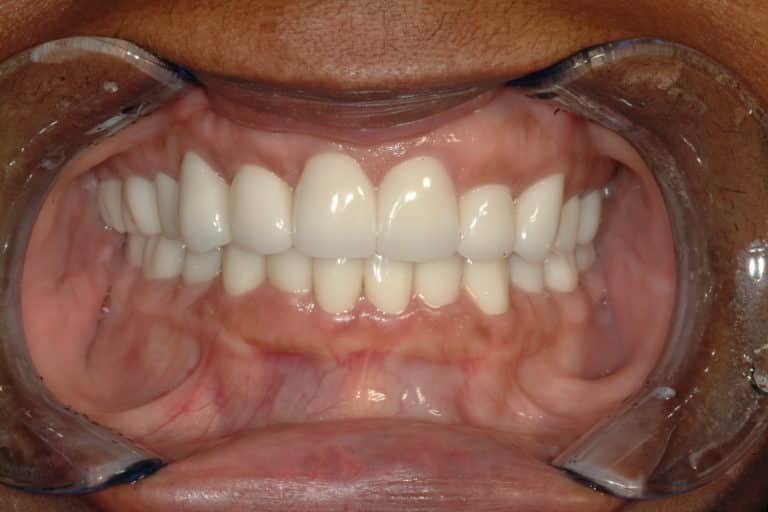

Before & After Gallery

Individual results may vary.